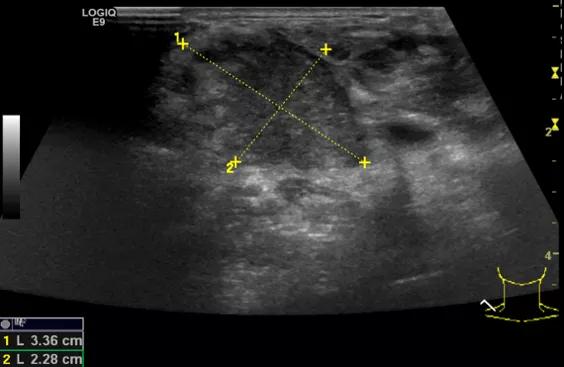

第四例是胸腺癌化妆包,术后、化疗之后淋巴结转移,肿块范围巨大,99mm*61mm,边界不清,呈浸润状,肿块包绕颈动脉,颈内静脉压闭,症状明显。由于患者放化疗也不敏感、血供非常丰富,于是采取多点姑息性消融。姑息性消融后未实现完全消融,病灶大片坏死,肿胀疼痛得到明显的缓解,后续患者未再来复查。

(病例4图例)